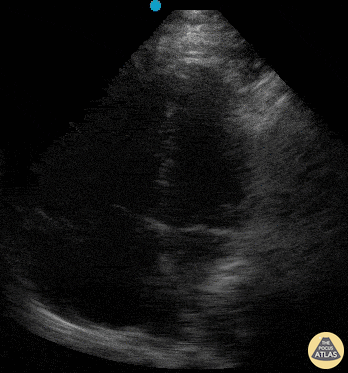

Right Ventricular Dysfunction - Clot in Transit

38 yo previously-healthy male 8 days s/p ligamentous repair of the knee, presented with dyspnea and chest pain. Physical exam on room air notable for tachypnea (RR 35), hypoxia (O2 sat 89%), and lungs that were clear to auscultation. POCUS revealed intracardiac thrombus with D-sign and McConnell's Sign. Pt received full-dose anticoagulation prior to CTA-PE confirming the suspected diagnosis of PE. He subsequently underwent successful thrombectomy. Stacey Frisch, MD Chief Resident, Emergency Medicine Kings County Hospital/SUNY Downstate @emergenStacey